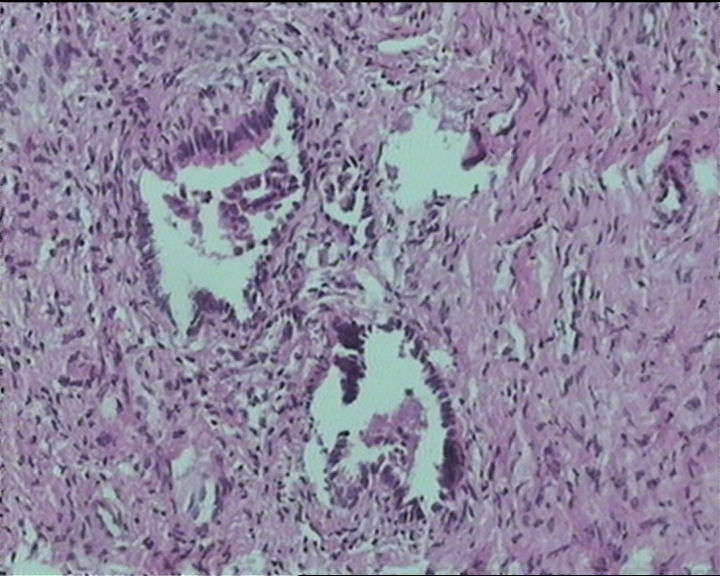

54岁女性,临床“宫颈息肉”送检;巨检:组织一块1。5*1CM,灰红。